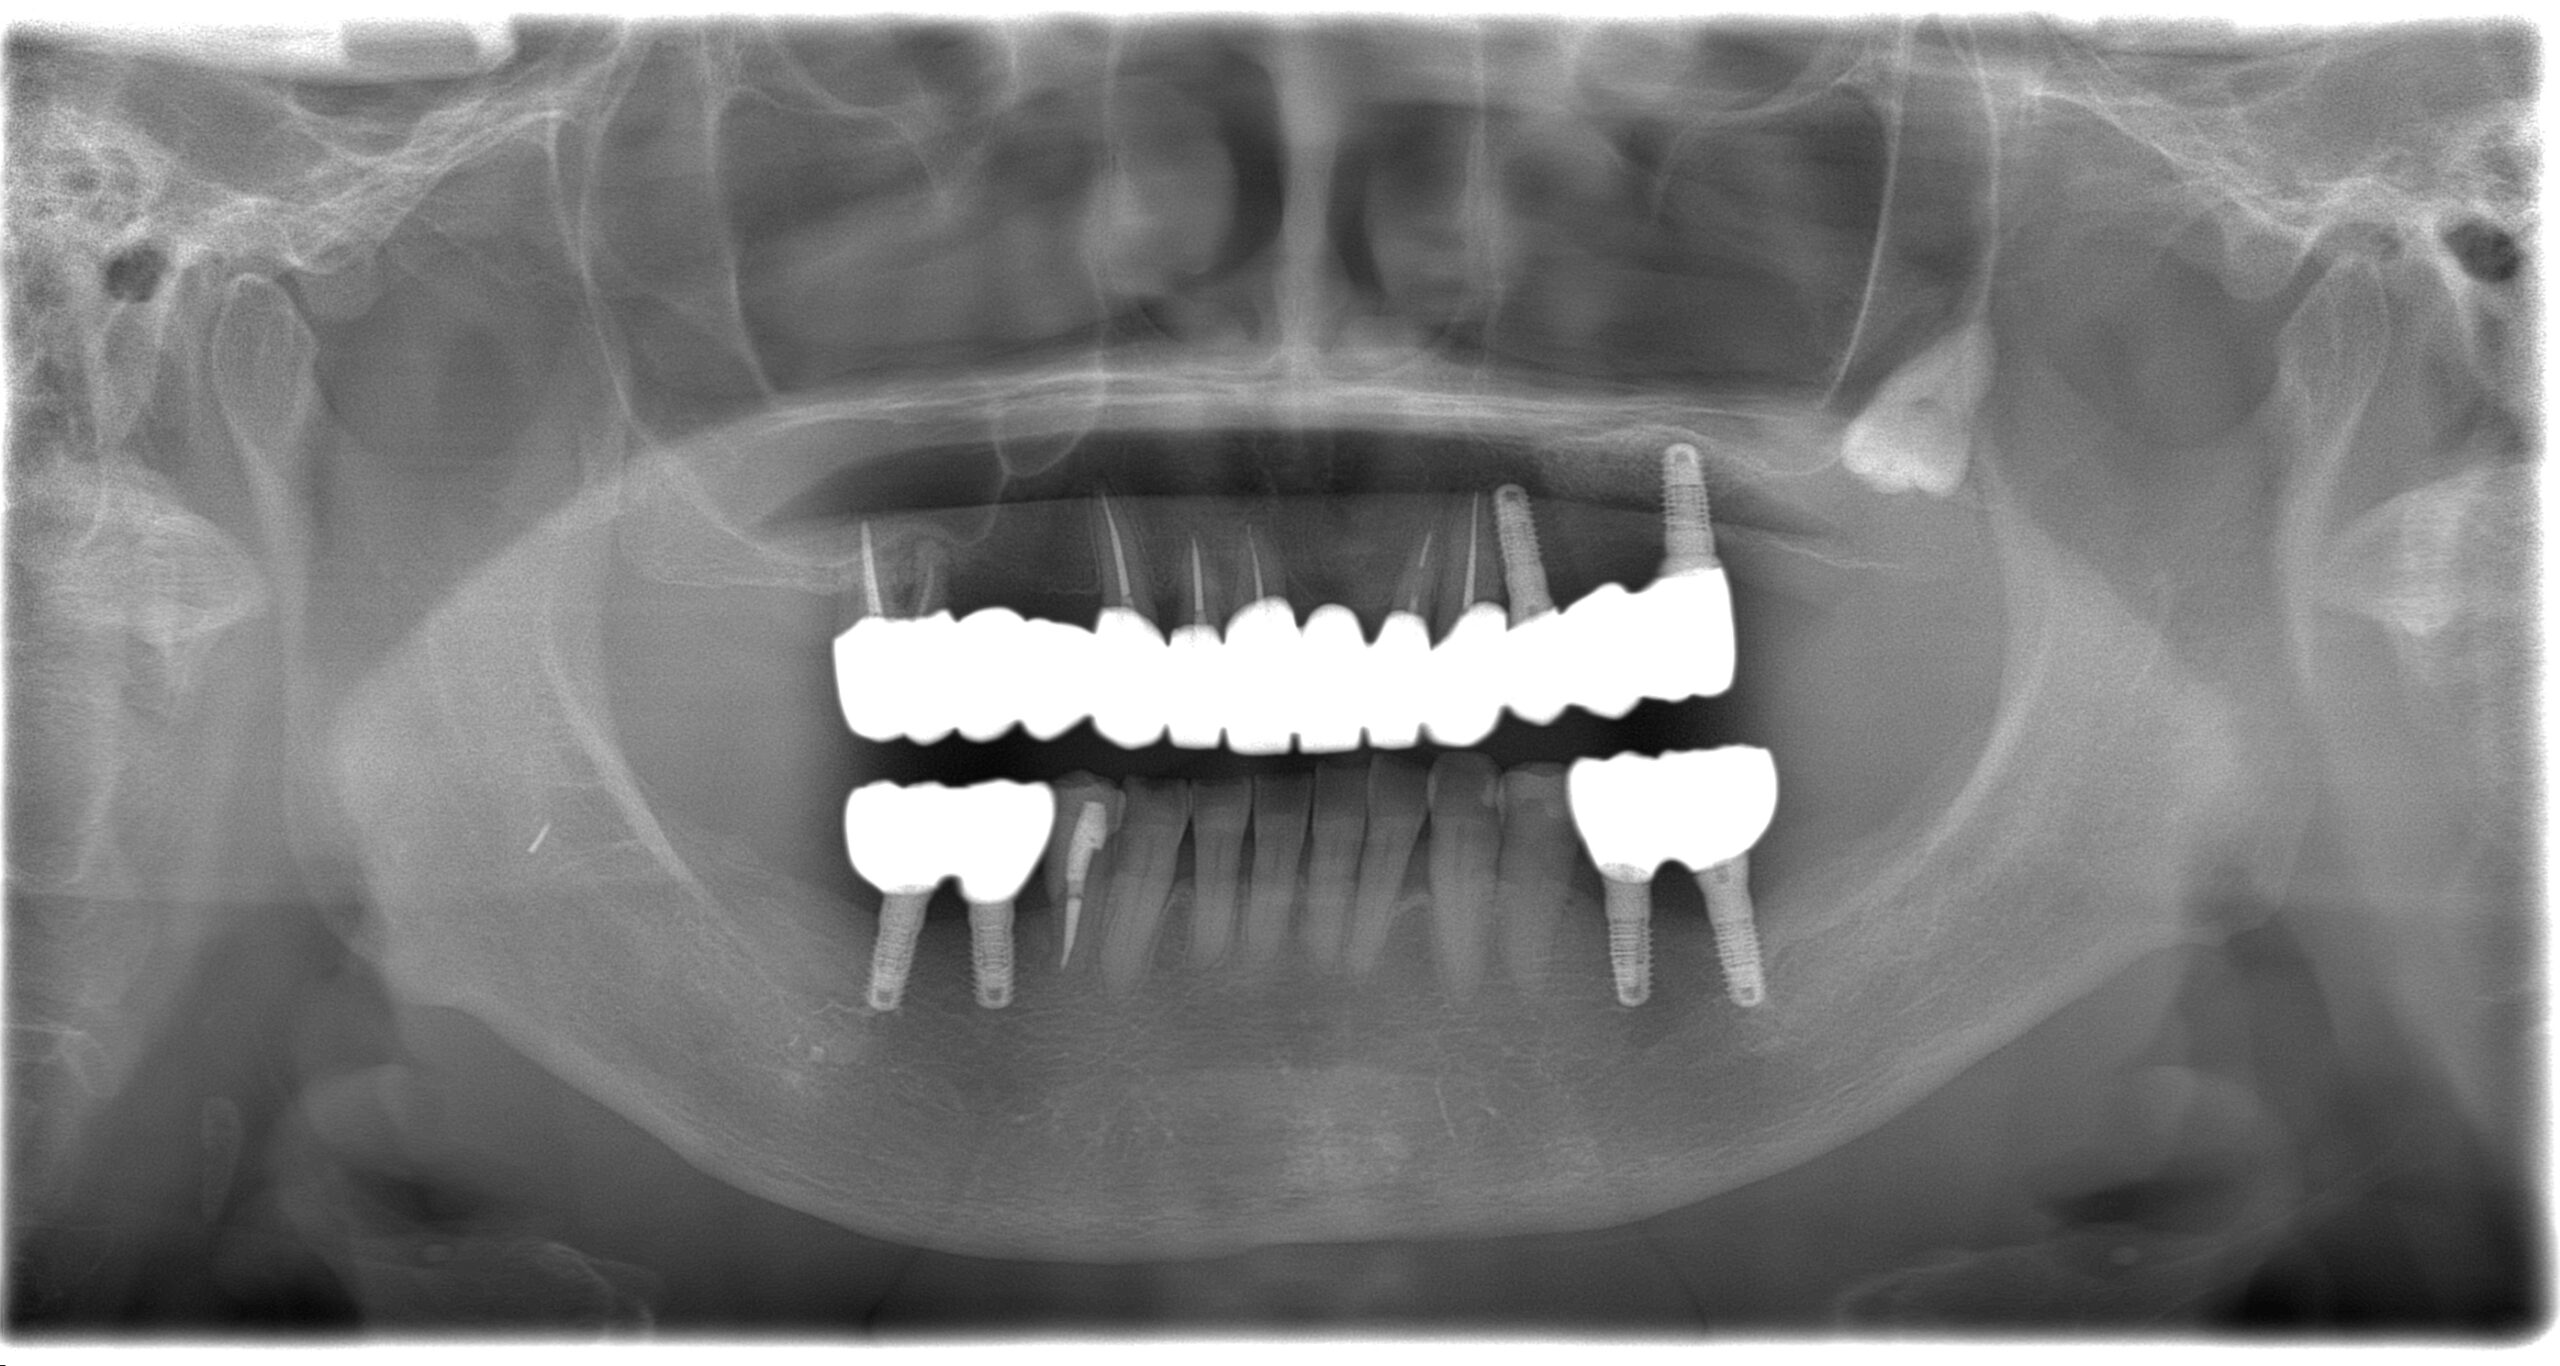

BEFORE

AFTER

主訴

全体的に見た目を綺麗にしたい。奥歯でしっかり噛みたい。

診断名・主な症状

臼歯部欠損

年齢

65歳

治療内容

インプラント埋入(左下5・6,右下5・6,左上4・6)

サイナスリフト(左上4・6)

ジルコニアBr(右上6−左上3)

E –MAX CAD(右下4)

セラミックインレー(左下4)

治療期間/

通院回数

約1.5年/約20回

費用

インプラント治療 約2,000,000円

その他被せ物治療など 約1,000,000円

合計 約3,000,000円

*いずれも税込